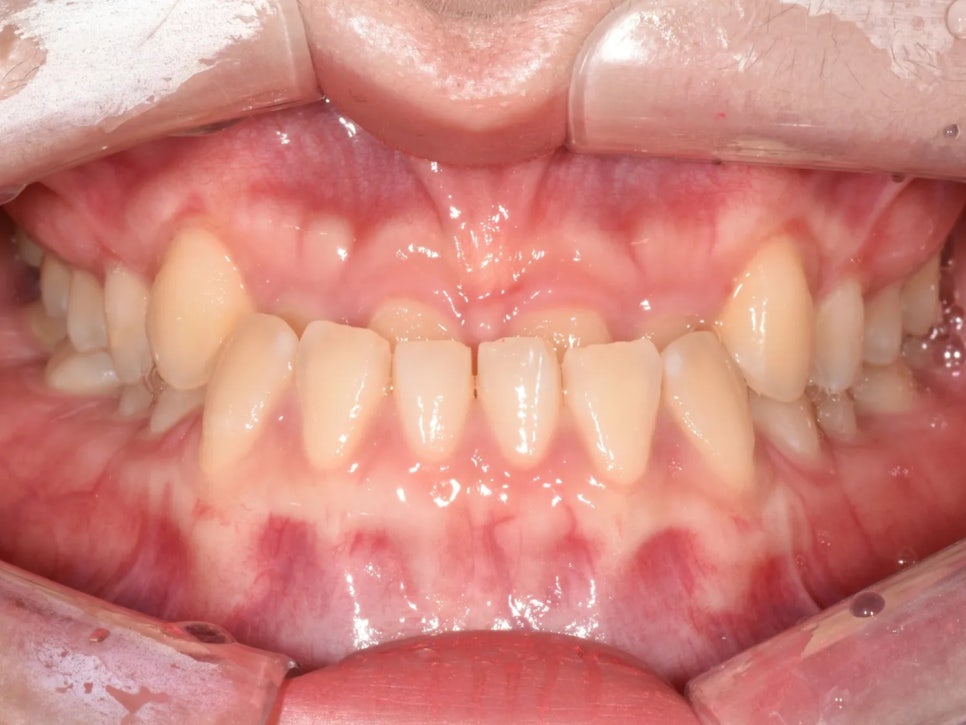

오늘 소개해 드릴 환자분은 30대 초반 여성으로, 주걱턱과 반대교합이 주된 고민이셨습니다.

먼저 입 안 사진을 보시면, 앞니 부분의 반대교합이 뚜렷하게 관찰됩니다. 윗 앞니가 아랫 앞니 뒤쪽으로 물리고 있는 상태예요.

아랫니가 윗니보다 나온 반대교합인데, 물리는 깊이도 깊은 과개교합 상태